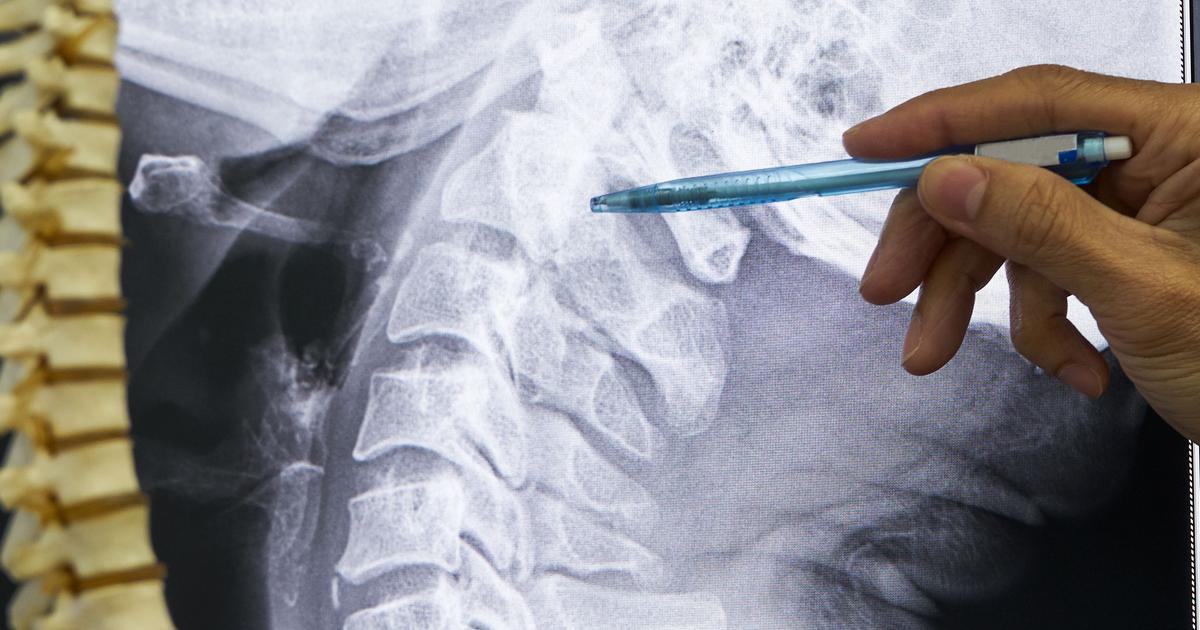

Spinal cord injury describes any damage that occurs to any region of the spinal cord or the lower spinal canal nerves. Spinal cord injuries can permanently alter an affected individual's sensations, strength, and any other functions of their body that involve nerves located underneath the site of their injury. General symptoms that occur with a spinal cord injury include movement loss, sensation loss, abnormal sensations, bladder or bowel incontinence, pain, breathing difficulty, exaggerated reflexes, and changes in sexual function. Most spinal cord injuries are the result of motor vehicle accidents, violence, sports, disease, alcohol, and falls. Diagnosis of a spinal cord injury can be made using X-rays, CT scans, and MRI. Treatment revolves around improving quality of life and preventing further injury since there is no way to reverse spinal cord damage.

When an individual incurs damage to the part of the spinal cord above the shoulders and closest to the neck and head, it is referred to as a cervical spinal cord injury. An individual's C1 to C7 vertebral levels make up their cervical spine, with C1 to C4 being the high-cervical nerves and C5 to C8 being the low-cervical nerves. Cervical spinal cord injuries compared to other types of spinal cord injuries are the most severe and result in the most loss of function. When an individual experiences a spinal cord injury at the C1 or C2 level, it is usually fatal. Quadriplegia or full paralysis typically result from spinal cord injuries at the C3 or C4 level. Individuals who experience a spinal cord injury between the C5 and C8 levels may be able to retain the ability to speak normally and breathe on their own but lose limb functionality. An individual who survives a cervical spinal cord injury may be unable to control bladder function, bowel function, and groom or dress themselves. Most patients who have a cervical spinal cord injury require twenty-four-hour care long term, if not for the rest of their life.